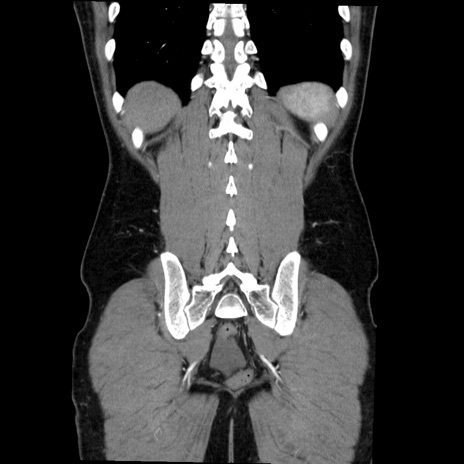

症例36(冠状断像)

【症例】20歳代 男性

【主訴】心窩部痛

【現病歴】今朝より上腹部痛あり。一旦軽快していたが再度出現したため救急要請。昨日夕に白身の魚を含む刺身を食べた。

【身体所見】BP 136/89mmHg、HR 74/min、BT 37.0℃、腹部:膨満、軟、心窩部に圧痛あり。反跳痛なし、筋性防御なし、腸雑音やや亢進あり。

【データ】WBC 17700、CRP 0.48